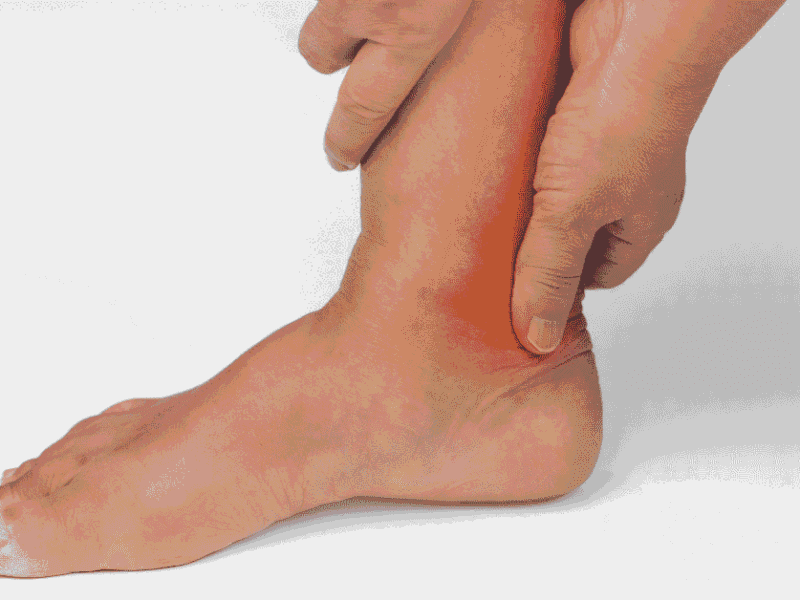

Foot and Ankle Arthritis: Symptoms, Causes, and Relief Tips

Arthritis is a common condition that affects millions of people worldwide, causing pain, stiffness, and reduced mobility in various joints, including those in the feet and ankles. While arthritis is often associated with aging, it can affect individuals of all ages, especially those with certain risk factors or underlying conditions. The feet and ankles, being [...] Read More